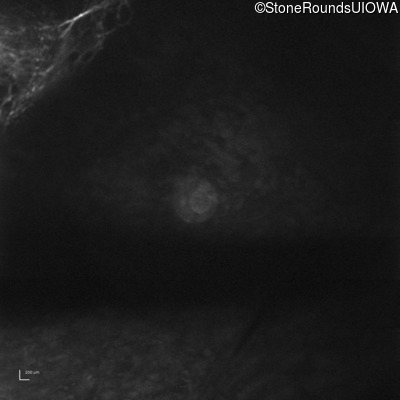

Optical Coherence Tomography - Right - 20/200 sc

Exemplar / OCT Stack